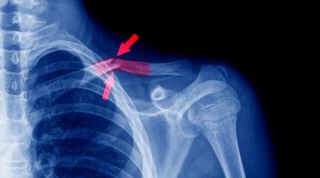

Seguidamente el especialista indicará estudios de imagenología como rayos X para confirmar el diagnóstico, así como también pueden ser necesarios procedimientos de imagen adicionales como la tomografía computarizada (TC) o la resonancia magnética (RM), para obtener no sólo un diagnóstico certero, sino el diseño de un plan terapéutico apropiado para el caso, ya que mediante ellos es posible detectar otras lesiones concomitantes a la fractura de clavícula, que requieran tratamiento.